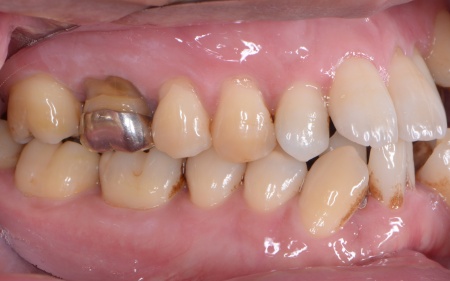

40代男性 乱れた歯並びと重度歯周病をワイヤー矯正と歯周再生療法で治療した症例

拝見したところ、上下の歯は、ずれたりねじれたりしてデコボコに生えており、著しく歯並びが乱れていました。

さらに、左下奥歯は重度の歯周病であり、歯を支えている骨が一部溶けていることが判明しました。

このまま放置すると骨がさらに溶け、歯を残すことが難しくなるおそれがあります。

②矯正治療後、歯周病を発症している左下奥歯(第1大臼歯)を温存するために、失われた骨や歯茎を再生する「歯周再生療法」を行う